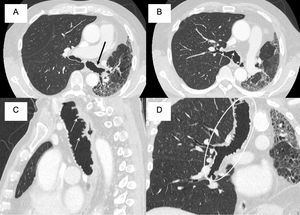

We present the case of a 72-year-old patient with a history of right lung transplantation (February 2018) treated with tacrolimus and rapamycin, who in October 2024 presented deterioration of lung function. A thoracic CT scan was performed in which tracheobronchial involvement was observed, with irregularity of the posterior wall of the trachea and bronchi, and formation of saccular dilations and tracheal pseudomembranes (Fig. 1). All this suggested a pseudomembranous tracheobronchitis secondary to subacute fungal infection. A bronchoscopy confirmed the presence of Aspergillus terreus, and treatment with isavuconazole and inhaled voriconazole was administered. Pseudomembranous tracheobronchitis is a condition in which pseudomembranes form in the trachea and bronchi, obstructing the airways and making it difficult to breathe. Its etiology can be bacterial, fungal, or related to connective tissue diseases. Chest CT scans show thickening of the tracheal and bronchial walls (Fig. 1), pseudomembranes (Fig. 1), airway obstruction, and pulmonary involvement such as atelectasis or consolidation [1]. Treatment is based on identifying the cause and giving appropriate treatment [2–4].

(A, B) CT scan showing formation of saccular dilations and tracheal pseudomembranes on the trachea and main bronchi (black and white arrows). (C) CT scan in a sagittal view showing affectation of the anterior and posterior walls of the trachea (white arrows). (D) MPR reconstruction of the trachea and right main bronchus showing an extensive mural disease (white ellipse).